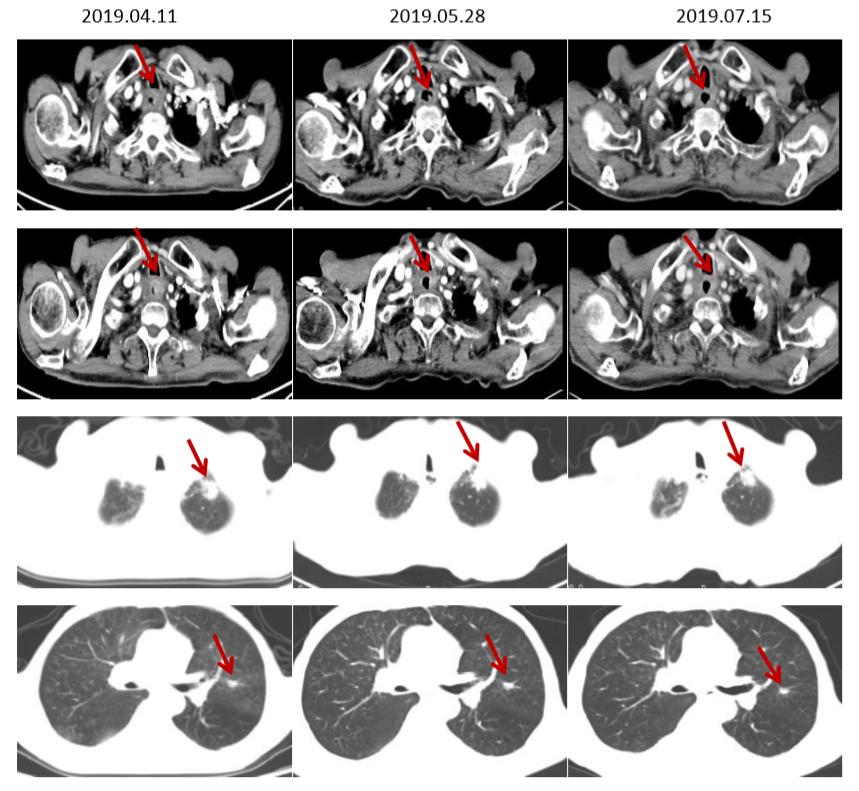

CT(脑转移治疗前后食管病灶及肺转移灶对比,部分肺转移灶较前增大)

CT(食管增厚较前明显改善,肺转移灶较前缩小)

MRI(颅内转移灶持续缩小)